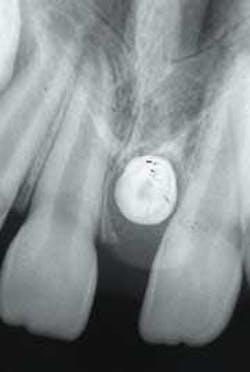

After a thorough clinical examination, four bite-wing radiographs and a panoramic film were ordered. In addition, a periapical film was ordered to examine the diastema area between the maxillary central incisors. Examination of the periapical radiograph revealed a dense tooth-like radiopacity surrounded by a radiolucent rim (see radiograph). The radiopacity was also apparent on the panoramic film.

As viewed on a dental radiograph, the mesiodens appears as a tooth-like radiopacity. This tooth-like radiopacity may appear rudimentary or conical in shape, or, resemble teeth normally found in the region. The size may vary from normal to miniature.

The diagnosis of a mesiodens is based on its radiographic appearance. On a good quality radiograph, the outline of a tooth and the radiolucent shadows of the pulp cavity and surrounding follicle are characteristic for the mesiodens.